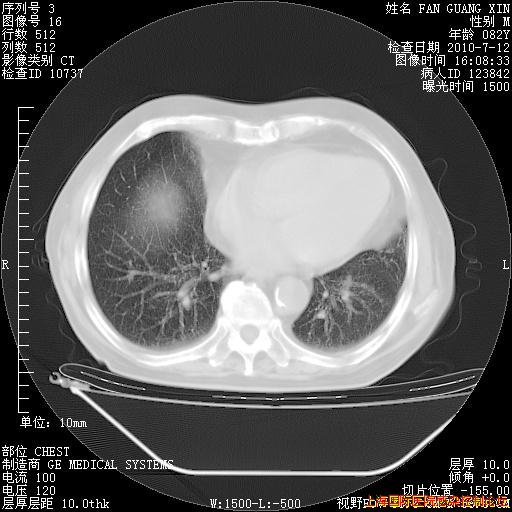

今天CT

整整相隔30天的肺部CT好像有所好转啊。甲强龙减量第3天,需要观察体温。